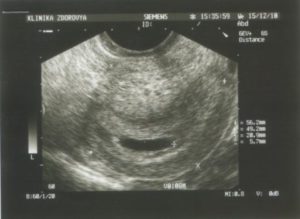

При помощи УЗИ гинеколог сможет увидеть не только угрозу, но и ее возможную причину (аномалия развития плода, предлежание и отслойку плаценты, признаки внутриутробного инфицирования, нарушение кровотока). При ультразвуковом исследовании всегда можно оценить состояние малыша и если потребуется, принять все возможные меры по сохранению беременности и спасению жизни плода.

Доктор произведет осмотр, во время которого оценит состояние матки и шейки матки, а также назначит УЗИ для оценки состояния плода.

Именно поэтому после того как случился выкидыш обязательно необходимо выполнить контрольное ультразвуковое исследование органов малого таза, чтобы убедиться в отсутствии в матке тканей плода. Если они были обнаружены, то потребуется выполнение гинекологической чистки.